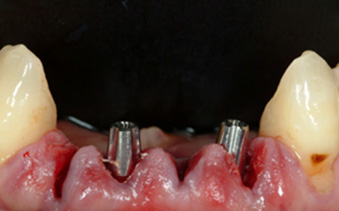

Extraction of the 4 lower incisors and simultaneous placement of two Ankylos implants for immediate loading of a 4 unit bridge (Fig.1)

Figure 1